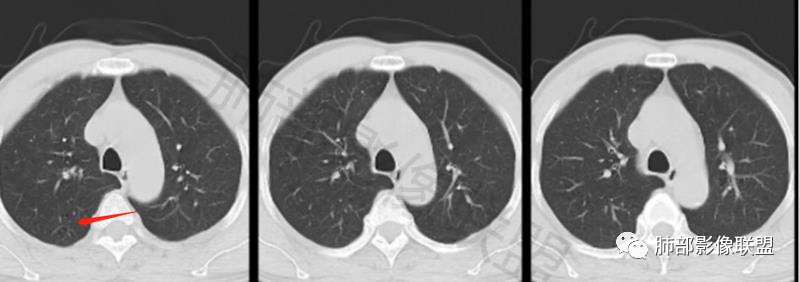

男,60体检发现左肺下叶结节,左肺下叶类圆形结节影,边界清晰,边缘见浅分叶及细短毛刺,病灶内见增粗血管影穿行,相应层面胸膜增厚,双肺另见微小结节影,增强扫描病灶轻度强化,考虑隐球菌,除外腺癌。

老年男性,左肺下叶背段胸膜下孤立结节,整体圆顿,周围有晕,晕中毛刺,似乎支持隐球,但边缘有一囊腔,恶性不能除外!等答案!

左下肺、右中肺均有结节,左下肺病灶比较鼓,边缘有晕,血管弯,持续性强化,考虑腺癌可能,鉴别两处病灶如果一元论,肉芽肿炎 (隐球)

左肺下叶胸膜下实性小结节,边缘可见毛刺,轻度收缩,近端与血管束相连,远端轻度牵拉胸膜,并远端可见小空泡,平扫密度均匀,增强后渐近性强化,考虑腺癌,鉴别隐球菌

老年男性,CT左肺下叶胸膜下类圆形结节,边缘光滑,无分叶,可见毛刺,相邻胸膜多条牵拉,局部胸膜增厚,(多见炎性病变),病灶周围可见模糊晕征,血管支气管进入,考虑隐球菌,现实中万万不能排除肺癌。

中老年男性患者,无症状体检发现,胸部CT:左下肺内前基底段近胸膜下类圆形结节,边缘清晰,周围晕征,周围毛刺细软,有胸膜牵拉及血管进入,增强扫描明显不均匀强化,考虑炎性肉芽肿,隐球菌可能,鉴别腺癌

图做的真漂亮!老年男性,双肺多发结节,最大者位于左肺下叶胸膜下,周围有晕,晕中毛刺,边缘有一囊腔,胸膜牵拉,持续强化,考虑隐球,鉴别腺癌。

老年男性,查体发现,左肺下叶靠近胸膜下结节,边缘膨隆,胸膜牵拉,有细软毛刺,周围有空泡征?中度强化,有血管进入,收缩力不强感觉,我也考虑隐球菌,鉴别肺癌,粘液腺癌?

左肺下叶胸膜下类圆形结节,边缘光滑,周围有晕,晕中有毛刺,周围可见小卫星灶,相邻胸膜增厚,血管进入,右肺中叶可见小结节影,考虑炎性肉芽肿,隐球菌。鉴别腺癌。

晨读:左肺下叶胸膜下实性小结节,边缘可见模糊晕及毛刺,轻度收缩,与支气管关系不清,近端与血管束相连,内见小空泡,平扫密度均匀,均匀强化。远近可见多个小结节。考虑炎性肉芽肿,隐球菌病,鉴别结核、腺癌。

老年男性,左肺下叶背段胸膜下结节,边缘毛刺,血管进入,斜裂有牵拉,局部胸膜糊墙,周围有晕,但有一囊腔,首先考虑腺癌,但是右肺中叶及左肺下叶还有其他结节,鉴别隐球菌